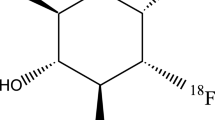

Since their first description by Alois Alzheimer himself, amyloid plaques represent one key hallmark for the diagnosis of Alzheimer’s disease. Until very recently, definite diagnosis of Alzheimer’s disease has only been possible by means of postmortem histopathological assessment of brain tissue. The advent of tracers for amyloid imaging now allows the detection of this core pathology in vivo. Consequently, for the first time, noninvasive in vivo proof of amyloid deposition in the brain and longitudinal observation of the onset and course of this pathology became possible. A great number of studies on in vivo imaging of amyloid deposits in the brain have been performed with the tracer [11C]PiB [44]. These studies form the basis of our current knowledge on the potential value of amyloid imaging in clinical practice. In addition, for a number of 18F-labeled tracers (with longer half-life), FDA approval has been achieved and they are now also commercially available. This includes [18F]florbetaben (NeuraCeqTM), [18F]florbetapir (AmyvidTM), and [18F]flutemetamol (VizamylTM) [45–47]. All tracers had to undergo extensive evaluation before approval, including in vivo versus postmortem evaluation of their properties [48–57].

For all tracers, typically intense tracer uptake is observed in the frontal, temporoparietal, and posterior cingulate cortex, the precuneus, and also the caudate nucleus. Sensorimotor and visual cortices are usually somewhat less affected and the cerebellum is spared of amyloid aggregates and, thus, can serve as a reference region [45, 47, 58, 59].